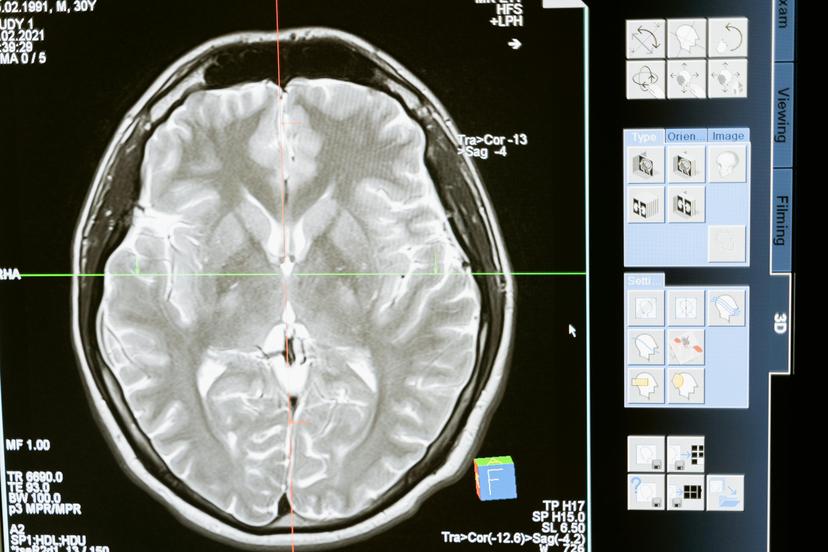

تفسير نتائج مخطط كهربية الدماغ

يعد تفسير نتائج تخطيط كهربية الدماغ (EEG) خطوة حاسمة في تشخيص الحالات العصبية وفهم وظائف المخ.. هذه نظرة عامة موجزة:

أ. فهم عادي مقابل. أنماط الموجات الدماغية غير الطبيعية

- عادي: يُظهر مخطط كهربية الدماغ الصحي أنماطًا محددة جيدًا مثل موجات ألفا وبيتا أثناء اليقظة وموجات دلتا أثناء النوم العميق.

- غير طبيعي: يمكن أن تشير المسامير غير المنتظمة أو الأنماط البطيئة أو عدم التماثل أو التشوهات البؤرية إلى حالات مثل الصرع أو إصابة الدماغ أو اعتلال الدماغ.

جي. دور طبيب الأعصاب في التحليل

يستخدم أطباء الأعصاب السياق السريري، والتعرف على الأنماط، ونتائج مخطط كهربية الدماغ لتشخيص الحالات العصبية ومراقبتها، وتوفير التوجيه العلاجي وتحسين رعاية المرضى..

- تفاصيل محدودة: لا يحدد مخطط كهربية الدماغ مشاكل الدماغ بدقة مثل التصوير بالرنين المغناطيسي.

- التصوير بالرنين المغناطيسي أو الأشعة المقطعية: توفر هذه البيانات بيانات تفصيلية عن بنية الدماغ، مع دمجها مع تفاصيل وظيفة مخطط كهربية الدماغ (EEG.